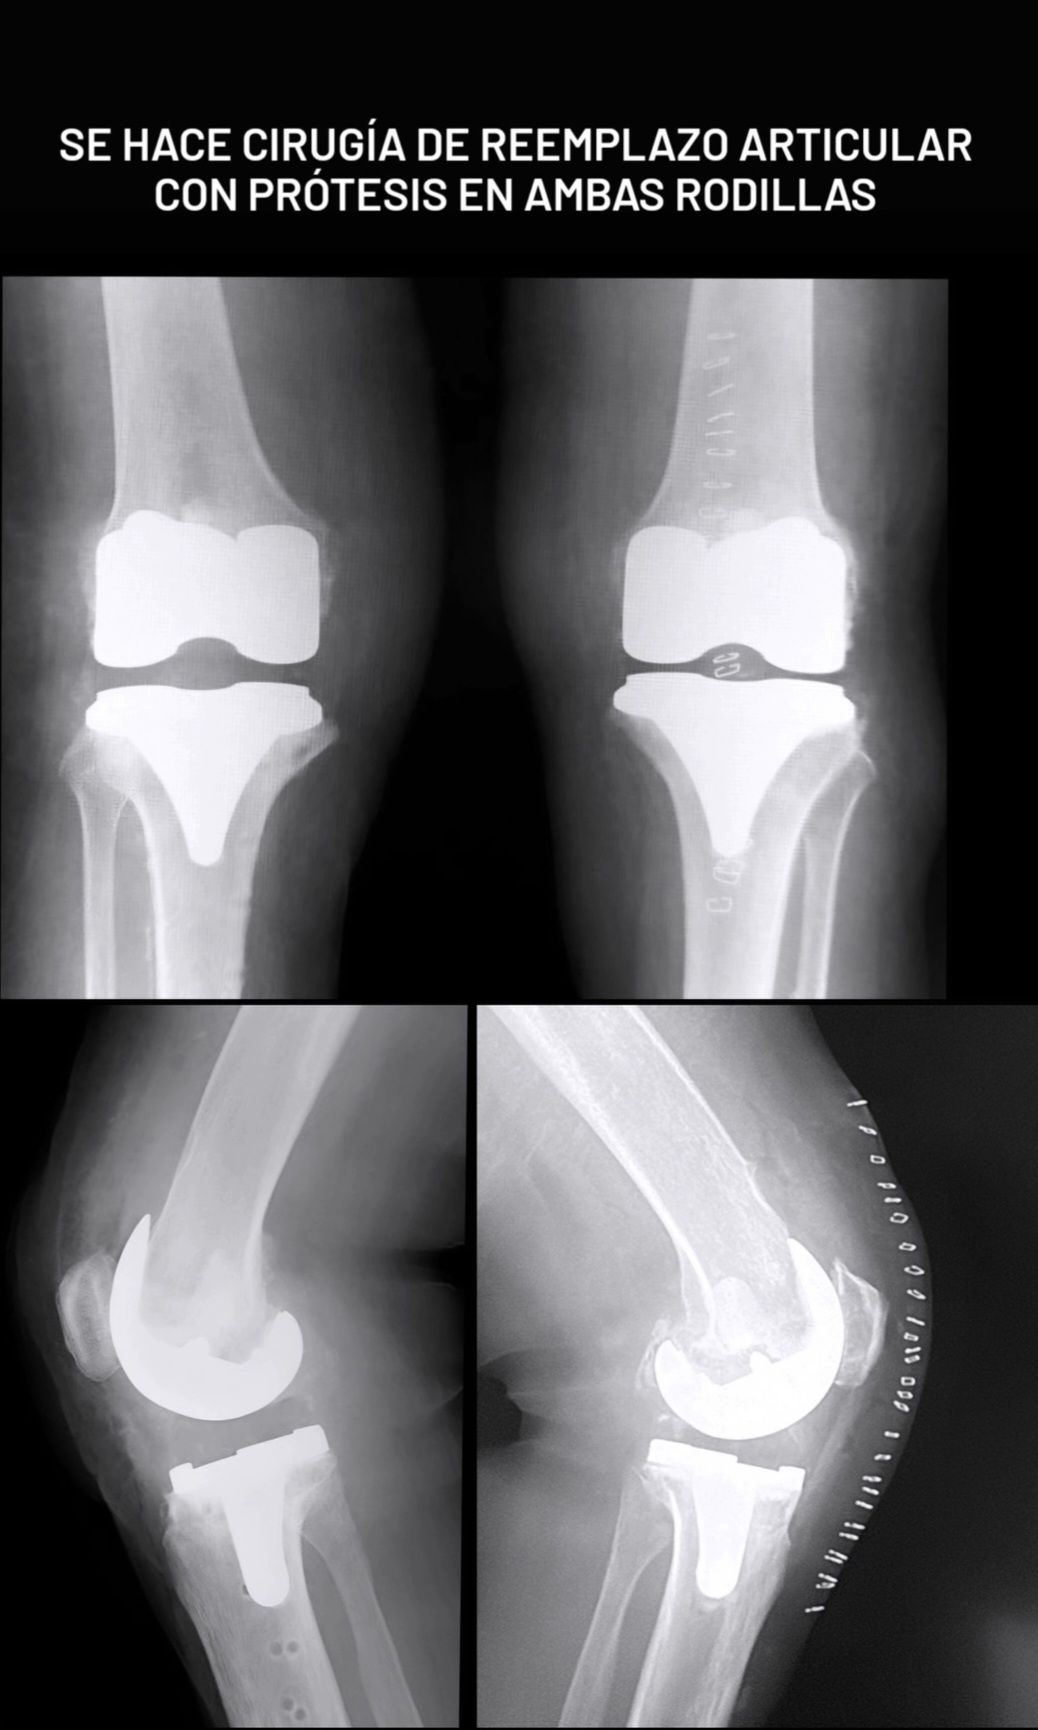

• Prótesis de Rodilla

Artroplastia rodilla con prótesis total Sin especificar